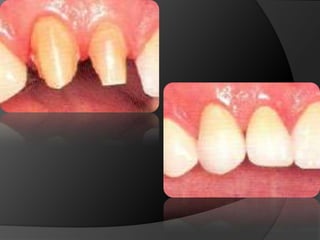

PRINCIPIOS ESTÉTICOSRestauraciones con forma, contorno y color adecuados

CARILLAS EN CERÁMICA: Alternativa menos agresiva cuando lo que se busca es el cambio de color o de forma en la superficie vestibular

PRINCIPIOS ESTÉTICOSRestauraciones conforma, contorno y color adecuados

CARILLAS EN CERÁMICA:Alternativa menos agresiva cuando lo que se busca es el cambio de color o de forma en la superficie vestibular